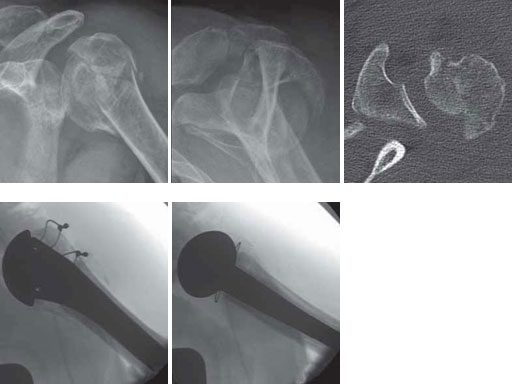

The EPOCA resurfacing head distinguishes itself not only by its anatomical geometry and its very thin surface, but also by its unique fixation design. A central crown anchors the hydroxyapatite coated prosthesis in a press-fit technique in the peripheral parts of the humeral head. In contrast to the central area which is used by most pegs fixed cups the peripheral area shows a better cancellous bone quality especially in osteoporotic conditions. To date, loosening of the EPOCA resurfacing head has not been observed in larger series (Fig 4).

67-year-old female with a primary omarthrosis on the right side.

Case provided by Norbert P Sdkamp, Martin Jaeger, Freiburg, DE, Ralph Hertel, Bern, CH

Fig 4ab Fracture situation in conventional x-rays.

Fig 4cd Implantation of a resurfacing head type EPOCA.